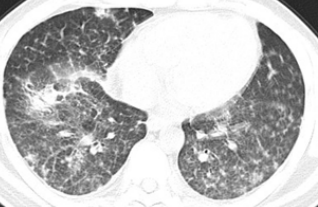

2017年10月5日胸部CT示左肺上叶结节影,边界光整,大小约11*12mm,两肺多发大小不等结节灶。

影像学检查

左肺上叶结节影,边界光整,大小约11*12mm,两肺见多发大小不等结节灶。

手术所见:胸腔镜下行肺叶部分(左肺上叶结节)切除术,术中探查见肿块约2*1.5*1cm大小,位于前段与舌段交界处。